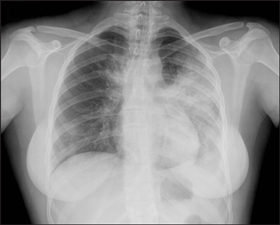

4 Chest x-rays showing typical abnormalities found in patients hospitalised with influenza, 17 June to 31 July 2009

Patient with pandemic (H1N1) 2009 influenza showing airspace opacity in the left upper and left lower lobes and medial right upper zone. |